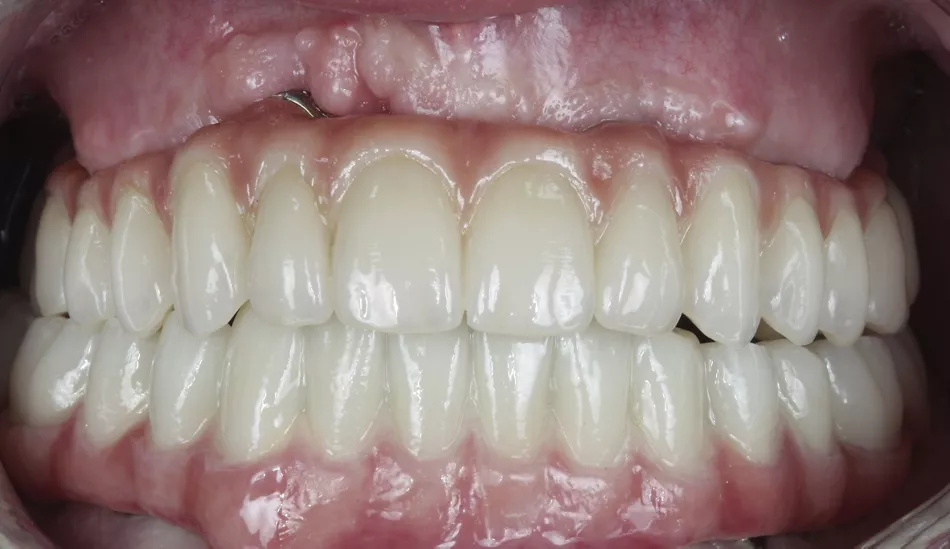

21. Front view of the finished case and placed with both structures screwed in the upper and lower jaw.

21